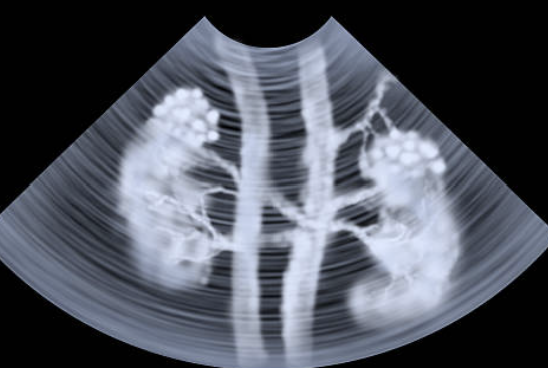

신장 초음파 검사 방법 신장 초음파 검사 하는 이유 등 신장 초음파와 관련된 정보를 정리해드리도록 하겠습니다. 신장 초음파 검사는 신장의 크기, 형태, 위치, 혈류 등을 살펴보는 검사입니다. 신장은 혈액을 정화하고, 물과 전해질의 균형을 조절하고, 호르몬을 분비하는 등 중요한 역할을 하는 장기입니다.

신장 초음파 검사는 어떻게 하는 것일까요? 신장 초음파 검사는 특별한 준비가 필요하지 않습니다. 단, 검사 전에 물을 충분히 마셔서 방광을 가득 채워야 합니다. 방광이 가득 차 있으면 신장의 이미지가 더 잘 나타납니다. 검사 시간은 약 15~20분 정도 걸립니다. 검사자는 침상에 누워서 배 부분을 드러내고, 의료진은 초음파 프로브라는 기기를 배 부분에 대고 움직입니다. 프로브에서 나오는 초음파가 신장에 반사되어 모니터에 신장의 이미지가 나타납니다. 의료진은 모니터를 보면서 신장의 상태를 판단합니다. 신장 초음파 검사는 통증이나 부작용이 없는 안전한 검사입니다.

신장은 신피질과 신수질로 구성되어 있으며, 각각 다른 에코를 보입니다. 에코란 초음파가 반사되는 정도를 말하는데, 일반적으로 신피질은 간이나 비장과 비슷하거나 약간 낮은 에코를 보이고, 신수질은 저에코를 보입니다. 이 두 부분의 경계가 명확하게 구분되어야 합니다. 만약 에코가 증가하거나 감소하거나, 경계가 불명확하거나, 내부에 공간을 차지하는 병변이 있으면 신장 질환의 징후일 수 있습니다. 예를 들어, 의료성 신장 질환, 침윤성 질환, 신결석, 신암 등의 경우에 에코 변화가 나타납니다.

신장 초음파 검사로 신장의 혈류도 확인할 수 있습니다. 신장은 신동맥과 신정맥으로 혈액을 공급받고 배출합니다. 신동맥은 신장의 후방에 위치하고, 신정맥은 신장의 중앙에 위치합니다. 이 두 혈관의 직경과 혈류 속도를 측정하여 혈관의 협착이나 폐쇄, 혈전, 동맥류 등의 이상이 있는지 확인할 수 있습니다. 예를 들어, 고혈압이나 당뇨병 등의 경우에 신동맥의 협착이나 경화가 발생할 수 있으며, 신암이나 신결석 등의 경우에 신정맥이나 하대정맥에 혈전이 발생할 수 있습니다.